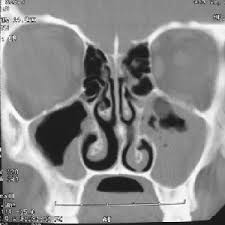

آنچه مىبینیم مجموعه اى از خطوط معوج به رنگ سفید است که به هم متصل و سطوحى را محصور کرده اند. تصویر تقریباً نسبت به خط فرضی اى که از بالا به پایین کشیده شده و از وسط آن مىگذرد، متقارن است. دو سطح خاکسترى رنگ در سمت راست و چپ بالاى تصویر و دو سطح مشکى متقارن در سمت راست و چپ پایین تصویر وجود دارد. ضمناً در میانه عکس، سطح باریکى از بالا به پایین کشیده شده است. این باریکه داراى خطوط معوج مشکى است که تقریباً نسبت به خط فرضى متقارن اند. دوست پزشکى که کنارمان نشسته است با لبخندى بر لب مىگوید: این تصویر بخشى از سر انسان است که با اشعه ایکس و به روش سىتى اسکن گرفته شده است. اکنون خطوط کمى برایمان با معنى تر مىشوند. طبق نظریه هاى اتمى که در فیزیک دبیرستانى یا سالهاى آغازین دانشگاه خوانده ایم، اشعه ایکس از گوشت و پوست عبور مىکند اما از استخوان نه. بنابراین هنگامى که یکى از اعضاى بدن در معرض آن قرار مىگیرد، تصویر استخوانهاى آن عضو بر روى فیلم رادیولوژى نقش مىبندد، تصویرى که استخوانها در آن به صورت خطوطى سفید دیده مىشوند. پس خطوط سفید تصویر فوق استخوانهاى سر یک انسان اند. احتمالاً قسمت میانى که به صورت طولى از بالا به پایین کشیده شده، همان بینى است. به نظر مىرسد که دو سطح خاکسترى سمت راست و چپ بالاى تصویر جاى چشمها باشند. از این رو، تصویر نسبت به خط فرضى اى که از بینى مىگذرد تقارن دارد. اما سطوح مشکى چه هستند؟

دوست پزشک ما براى گویاترشدن تصویر مىگوید این یک عکس رادیولوژى از سینوسهاى شخصى بیمار است. دو ناحیه مشکى ، سینوسها هستند که کنار بینى، زیر چشمان و بالاى آرواره زِبرین قرار گرفته اند. ناحیه خاکسترى اهمیت خاصى دارد. اگر عرض این ناحیه بیش از سه میلىمتر باشد، غیرطبیعى بودن سینوسها را نشان مىدهد. متأسفانه در عکس فوق، پهناى این ناحیه نشان از غیرطبیعى بودن سینوسهاى این فرد دارد. ضمناً مجارى موجود در ناحیه میانى ترشحات سینوسها را از راه بینى به بیرون هدایت مىکنند. همانطور که در تصویر ملاحظه مىشود، این مجارى مسدودند و همین باعث دردهاى شدیدى در ناحیه سر مىشود.

دوست پزشک ما بسیارى از چیزهایى را مىبیند که ما اصلاً بدانها توجهى نداشته ایم. چرا؟ زیرا او با نظریه هایى که عکسهاى سىتى اسکن را تعبیر و تفسیر مىکنند، آشناست و از تمام نظریه هاى پزشکى که به توصیف و تشخیص امراض گوش و حلق و بینى مىپردازند، آگاهى دارد. کار و هدف او تشخیص بیمارى است. از اینرو وقتى با تصویر سىتى اسکن فوق مواجه مىشود، به دنبال لکه ها و خطوطى مىگردد که نشانه عارضه اى در سینوسهاى فرد بیمار باشد تا با این روش بتواند بیمارى فرد را تشخیص دهد. ما نیز به میزانى که از این نظریه ها آگاه باشیم خطوط و لکه هاى روشن و تاریک تصویر برایمان داراى معنا خواهد بود و مىتوانیم برخى از مشاهدات پزشک درباره تصویر مزبور را بیان کنیم؛کما اینکه شناخت ما از اشعه ایکس و نظریه هاى مرتبط با آن سبب شد تا استخوانهاى سَرِ فرد و جمجمه او را تشخیص دهیم.